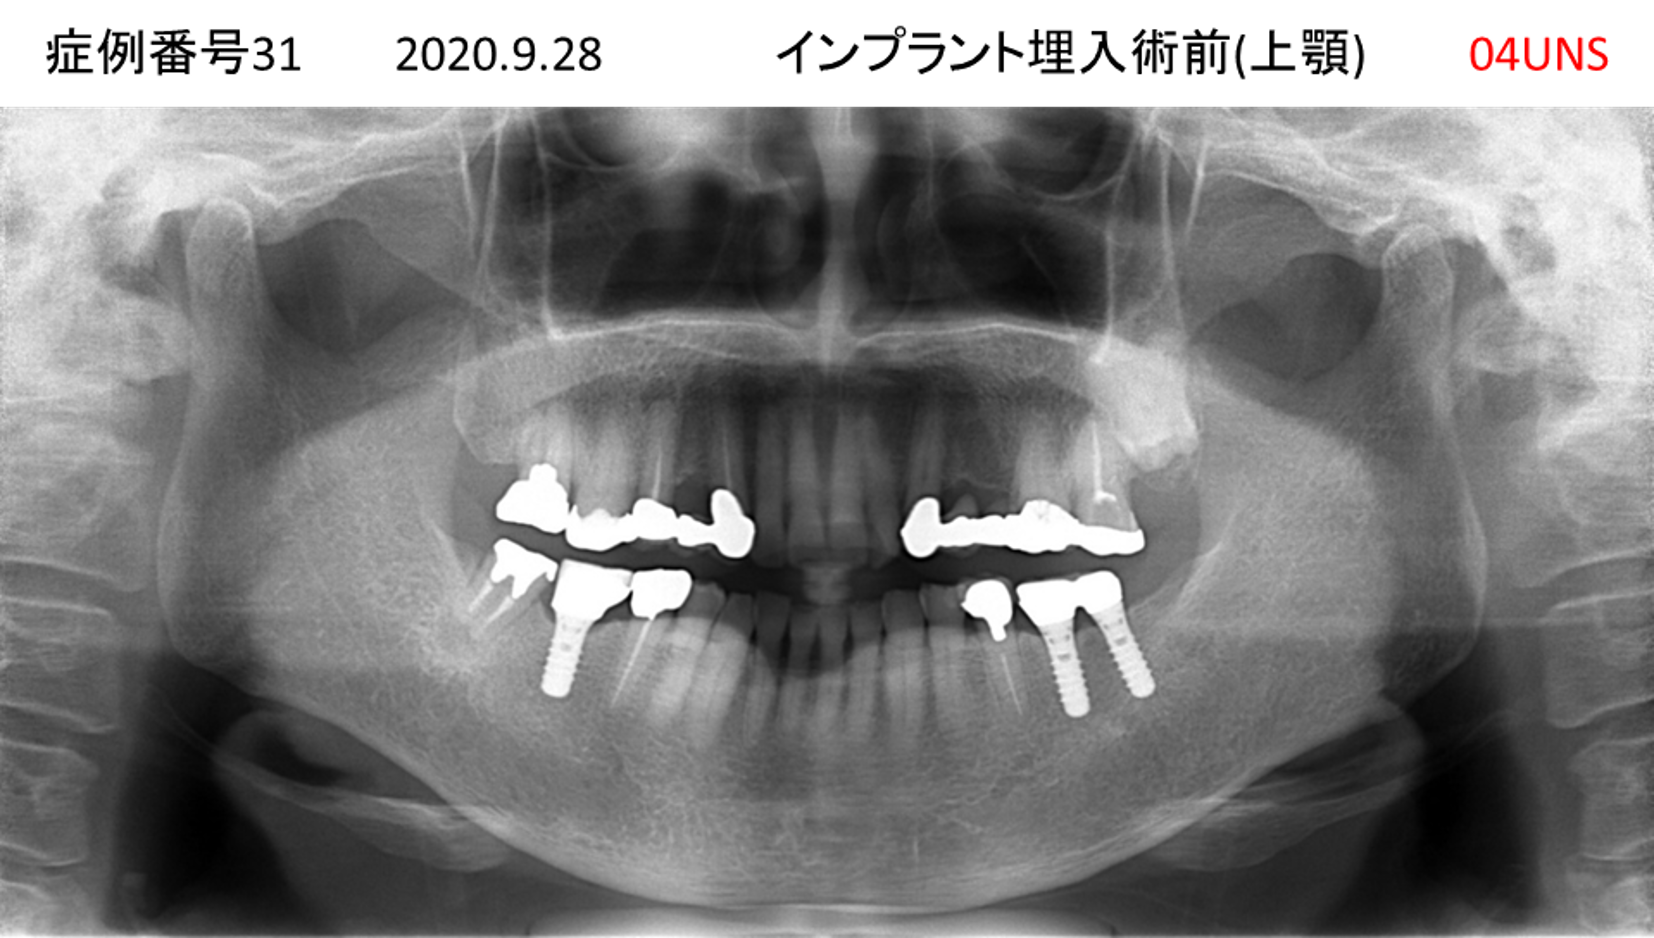

ご飯を美味しく食べたい/人前で笑えるようになりたい患者様のインプラント症例

| 治療名称 |

インプラント |

| 治療費用 |

480万円+税 |

| 治療期間 |

6か月 |

| 患者さんの症状(主訴) |

おいしいご飯が食べられるようになりたい 人前で笑えるようになりたい |

| 治療内容 |

サイナスリフト 抜歯即時インプラント |

| 治療結果 |

何でも食べられるようになった 人前で大口を開けて笑えるようになった |

| 治療の注意点(リスク/副作用) |

インプラントが壊れた場合は再治療が必要 |